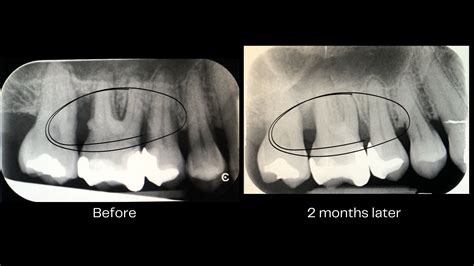

• Dental X-rays: Assessing the level of bone loss around the tooth roots, which is critical for determining the severity of the disease.

• Bone Grafting: If the bone supporting the tooth has been destroyed, a graft—using synthetic, donated, or the patient’s own bone—can be placed to stimulate new bone growth.

• Guided Tissue Regeneration (GTR): A barrier membrane is placed between the gum tissue and bone to allow the bone and connective tissue to grow back without being crowded out by the faster-growing gum tissue.